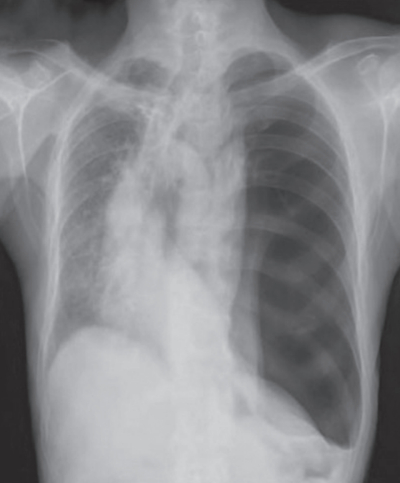

64歳の男性。呼吸困難を主訴に来院した。4日前に左胸痛と息切れが出現し、次第に増悪してきたため受診した。

体温36.2℃。脈拍100/分、整。血圧120/80mmHg。呼吸数20/分。SpO2 92%(room air)。眼瞼結膜と眼球結膜とに異常を認めない。頸部リンパ節を触知しない。左胸部に呼吸音を聴取しない。

血液所見:赤血球420万、Hb 13.0g/dL、Ht 37%、白血球4,400、血小板21万。CRP 0.4mg/dL。来院時の胸部エックス線写真を別に示す。入院後、胸腔ドレーンを挿入したところ、直後から咳嗽と泡沫状の喀痰が出現した。この時点の胸部エックス線写真を別に示す。

来院時